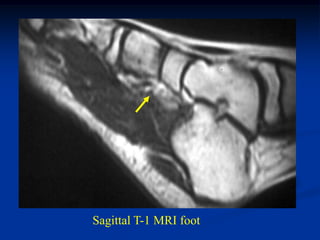

Hemangioma

Case #298.1

15 year male with tender

mass lateral side of forefoot

for many years

Axial T-1

T-2

Sag T-1

Cor T-2